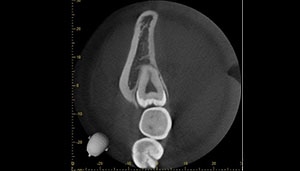

CT

CTで親知らずと神経(下歯槽管)の位置を確認しました。

親知らずと神経は一定の距離があり、麻痺などのリスクがほとんどないと判断できます。